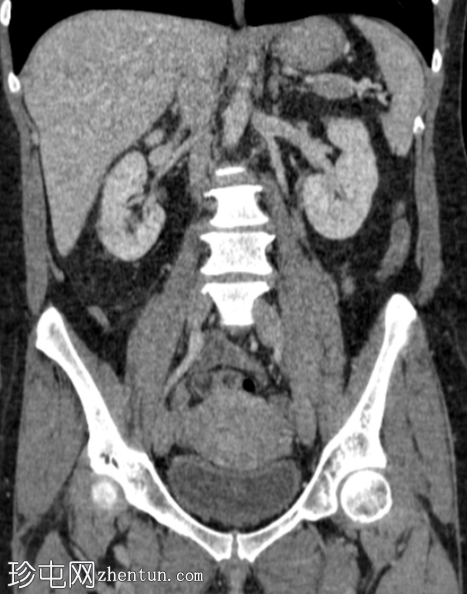

冠状位增强扫描(门静脉期)

右肾轴位和冠状位图像均显示肾实质下部低强化区域,伴肾周脂肪间隙模糊,符合急性肾盂肾炎的

影像

学表现。

肝脏散在少量微小囊肿。

胆囊底部局灶性腺肌瘤病。

左侧黄体囊肿。